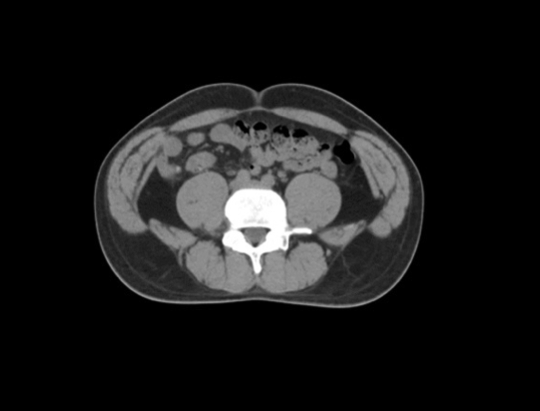

Z jednej strony niezbędne jest skrócenie czasu oczekiwania i zapewnienie pacjentowi jak najlepszych doświadczeń z leczenia. Z drugiej strony profesor Zhen napotyka w radioterapii wiele technicznych wąskich gardeł. Radioterapia jest uznawana za jedną z najlepszych metod leczenia nowotworów na świecie. Potrafi ona precyzyjnie zabijać komórki nowotworowe omijając zdrowe tkanki, co wymaga dostosowania leczenia do potrzeb każdego pacjenta, a także ścisłej koordynacji działań personelu medycznego w wielu obiektach i wykorzystania wielu urządzeń. Cały proces obejmuje sześć etapów: unieruchomienie pacjenta, symulowane pozycjonowanie, określenie obszaru docelowego, stworzenie planu radioterapii, kontrolę jakości planu, sterowanie obrazem i wdrożenie radioterapii. Każdy z tych elementów musi zostać przeprowadzony w bardzo rygorystyczny sposób, co wymaga czasu. „Czy można w fundamentalny sposób zoptymalizować ten proces, tak aby można było jednocześnie osiągnąć wysoką efektywność i precyzję?”- profesor Zhen przez lata szukała takiego rozwiązania.

„Pomysł ten przetestowano po raz pierwszy 2 marca 2021 r. o godzinie 9.00: lekarze, fizycy i technicy zebrali się w pomieszczeniu sterowniczym, aby wykonać u pacjenta z rakiem odbytnicy pierwszy zabieg przy użyciu kompleksowej technologii radioterapii All-In-One. Kolejno wykonano pozycjonowanie symulacyjne TK, inteligentną modyfikację obrysu i przegląd, automatyczne planowanie, automatyczny reset, ocenę i przegląd planu, sterowanie obrazem TK, terapię oraz kontrolę jakości, czyli monitorowanie dawki w czasie rzeczywistym z użyciem elektronicznego detektora obrazowego (EPID). Cały proces został ukończony w 23 minuty, podczas gdy pierwszy zabieg radioterapii prowadzony w sposób tradycyjny zająłby co najmniej kilka dni. Jest to nowy model leczenia nowotworów z wykorzystaniem technologii sztucznej inteligencji, który otwiera nową erę inteligentnej terapii onkologicznej.”